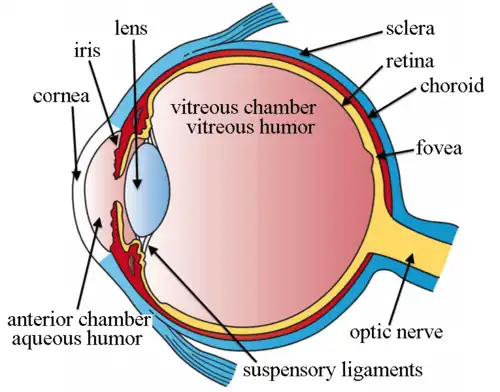

The eye can be considered as a living optical device. It is approximately spherical in shape, with its outer layers, such as the outermost, white part of the eye (the sclera) and one of its inner layers (the pigmented choroid) keeping the eye essentially light tight except on the eye's optic axis. In order, along the optic axis, the optical components consist of a first lens (the cornea—the clear part of the eye) that accounts for most of the optical power of the eye and accomplishes most of the focusing of light from the outside world; then an aperture (the pupil) in a diaphragm (the iris—the coloured part of the eye) that controls the amount of light entering the interior of the eye; then another lens (the crystalline lens) that accomplishes the remaining focusing of light into images; and finally a light-sensitive part of the eye (the retina), where the images fall and are processed. The retina makes a connection to the brain via the optic nerve. The remaining components of the eye keep it in its required shape, nourish and maintain it, and protect it.

The eye is not shaped like a perfect sphere; rather it is a fused two-piece unit, composed of an anterior (front) segment and the posterior (back) segment. The anterior segment is made up of the cornea, iris and lens. The cornea is transparent and more curved and is linked to the larger posterior segment, composed of the vitreous, retina, choroid and the outer white shell called the sclera. The cornea is typically about 11.5 mm (0.45 in) in diameter, and 0.5 mm (500 μm) in thickness near its centre. The posterior chamber constitutes the remaining five-sixths; its diameter is typically about 24 mm (0.94 in). An area termed the limbus connects the cornea and sclera. The iris is the pigmented circular structure concentrically surrounding the centre of the eye, the pupil, which appears to be black. The size of the pupil, which controls the amount of light entering the eye, is adjusted by the iris' dilator and sphincter muscles.

The eye is made up of three coats, or layers, enclosing various anatomical structures. The outermost layer, known as the fibrous tunic, is composed of the cornea and sclera, which provide shape to the eye and support the deeper structures. The middle layer, known as the vascular tunic or uvea, consists of the choroid, ciliary body, pigmented epithelium and iris. The innermost is the retina, which gets its oxygenation from the blood vessels of the choroid (posteriorly) as well as the retinal vessels (anteriorly).

The spaces of the eye are filled with the aqueous humour anteriorly, between the cornea and lens, and the vitreous body, a jelly-like substance, behind the lens, filling the entire posterior cavity. The aqueous humour is a clear watery fluid that is contained in two areas: the anterior chamber between the cornea and the iris, and the posterior chamber between the iris and the lens. The lens is suspended to the ciliary body by the suspensory ligament (zonule of Zinn), made up of hundreds of fine transparent fibers which transmit muscular forces to change the shape of the lens for accommodation (focusing). The vitreous body is a clear substance composed of water and proteins, which give it a jelly-like and sticky composition.[6]